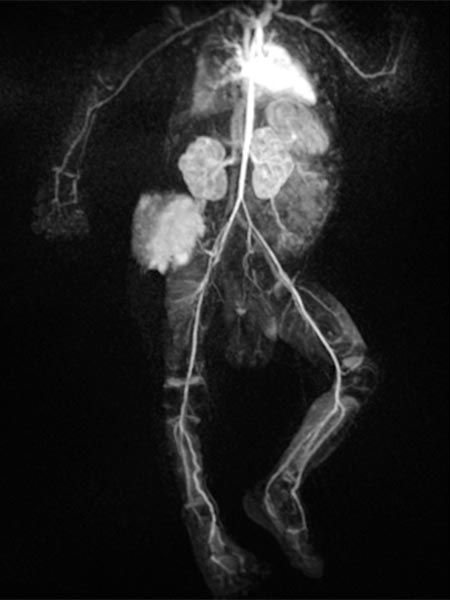

In the final control angiography with long series after injection into the right common iliac artery, the tumor is completely devascularized. The unaffected, physiological arterial branches of the surrounding tissue are all preserved. Thus, the tumor is completely eliminated from the circulation. Activation of coagulation and consumption of platelets in the tumor has stopped.